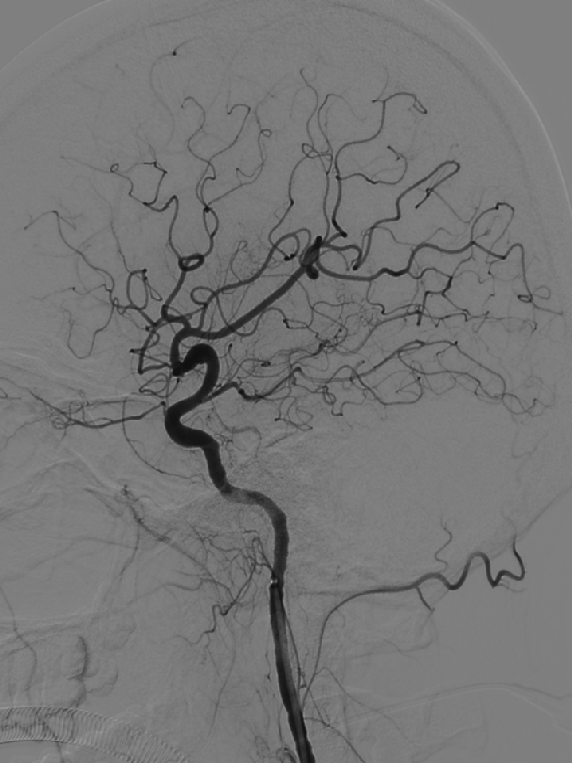

术后图像显示支架打开及贴壁良好。

术后工作位造影

术后侧位造影

术后正位造影

术后患者一般情况可,诉头疼,给予对症处理。神经查体:无阳性定位体征。给低分子肝素4100U皮下注射一次。继续口服阿司匹林100mg 1次/日,替格瑞洛90mg 2次/日。